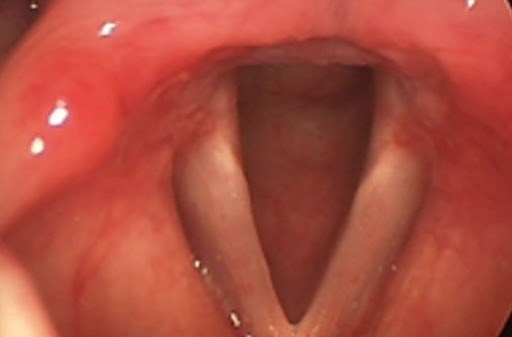

Ларингоскопическая картина через 1 месяц

По словам пациента, прекращение кашля произошло на 3-и сутки терапии.

По данным гистологического анализа – фиброзный полип гортани. Голос номализовался на 10 сутки после удаления полипа.

Пациент получает поддерживающую дозу Рабепразола, направлен к гастроэнтерологу. На контрольном осмотре через 6 мес – без рецидива.